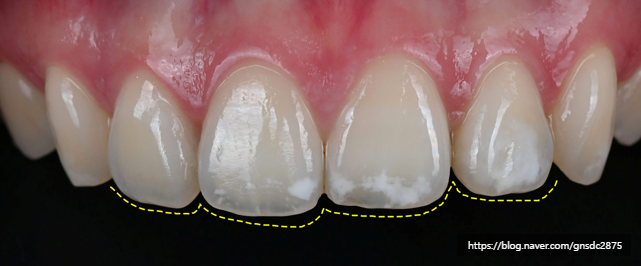

#CASE 03

백색반점이 있는 길이가 다른 앞니

세번째 케이스도 마찬가지로

양앞니와 옆치아까지 번진 백색반점을

뉴티스 반점치치료로 개선하고

울퉁불퉁 고르지 못한 치아 끝을

뉴티스 치아성형을 통해 고르게 개선하였습니다.